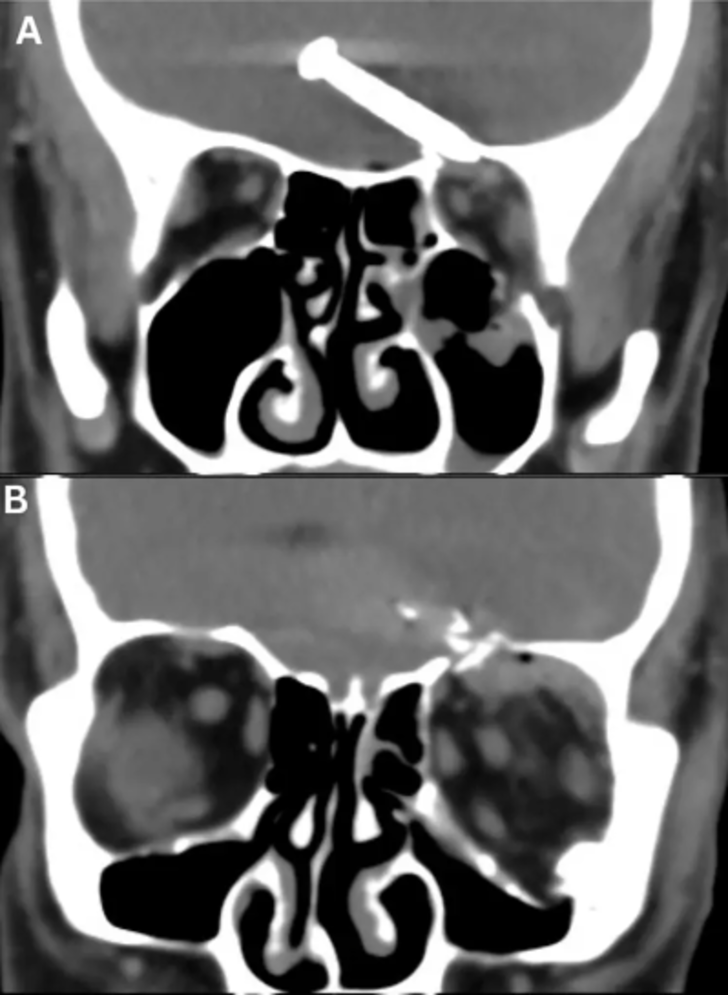

Röntgen görüntüleri, 3,2 cm büyüklüğündeki çivinin, hareket ve konuşma için hayati önem taşıyan beyninin ön lobunun derinliklerine saplandığını gösterdi.

Cureus tıp dergisinde yayınlanan araştırmaya göre, sol gözünün yan kantusunda (iki göz kapağının birleştiği yerde) yaralar ve sol yörünge tavanında ve tabanında kırıklar da vardı. Çalışma, çivinin bir şekilde hayati arterleri ve sinirleri ıskaladığını ve uzun vadeli herhangi bir hasardan kurtulduğunu söyledi. Hasta mucizevi bir şekilde hayatta kalırken görme yeteneğini de kaybetmedi.